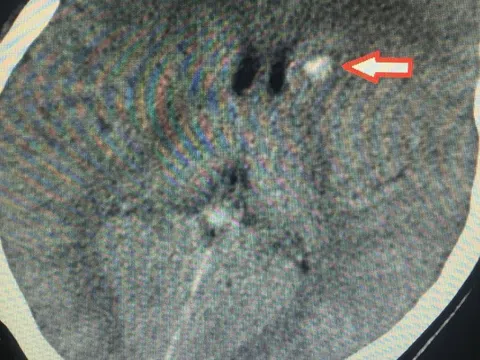

Hình ảnh u buồng trứng xoắn tím đen - Ảnh: BVCC

U buồng trứng nếu không được phát hiện kịp thời rất dễ gây biến chứng: xoắn cuống khối u, vỡ u, chèn ép các cơ quan xung quanh, biến thành u ác tính.

Một biến chứng khác là xoắn nang, xảy ra khi cuống nang dài làm nang di chuyển và bị xoắn. Nếu được chẩn đoán sớm và xử trí kịp thời, tiên lượng sẽ tốt, ngược lại khối u sẽ vỡ ra hoặc hoại tử và bệnh nhân có thể tử vong.